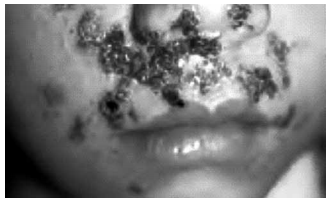

Pré-escolar de 4 anos de idade, com história de lesões em face há 5 dias, evoluindo com piora progressiva e aparecimento de febre (38 ºC). Ao exame físico, apresenta lesões vesiculares em base eritematosa e algumas lesões crostosas coalescentes ao redor da boca e do nariz e presença de linfoadenomegalia cervical. Veja a imagem.

A principal hipótese diagnóstica é: